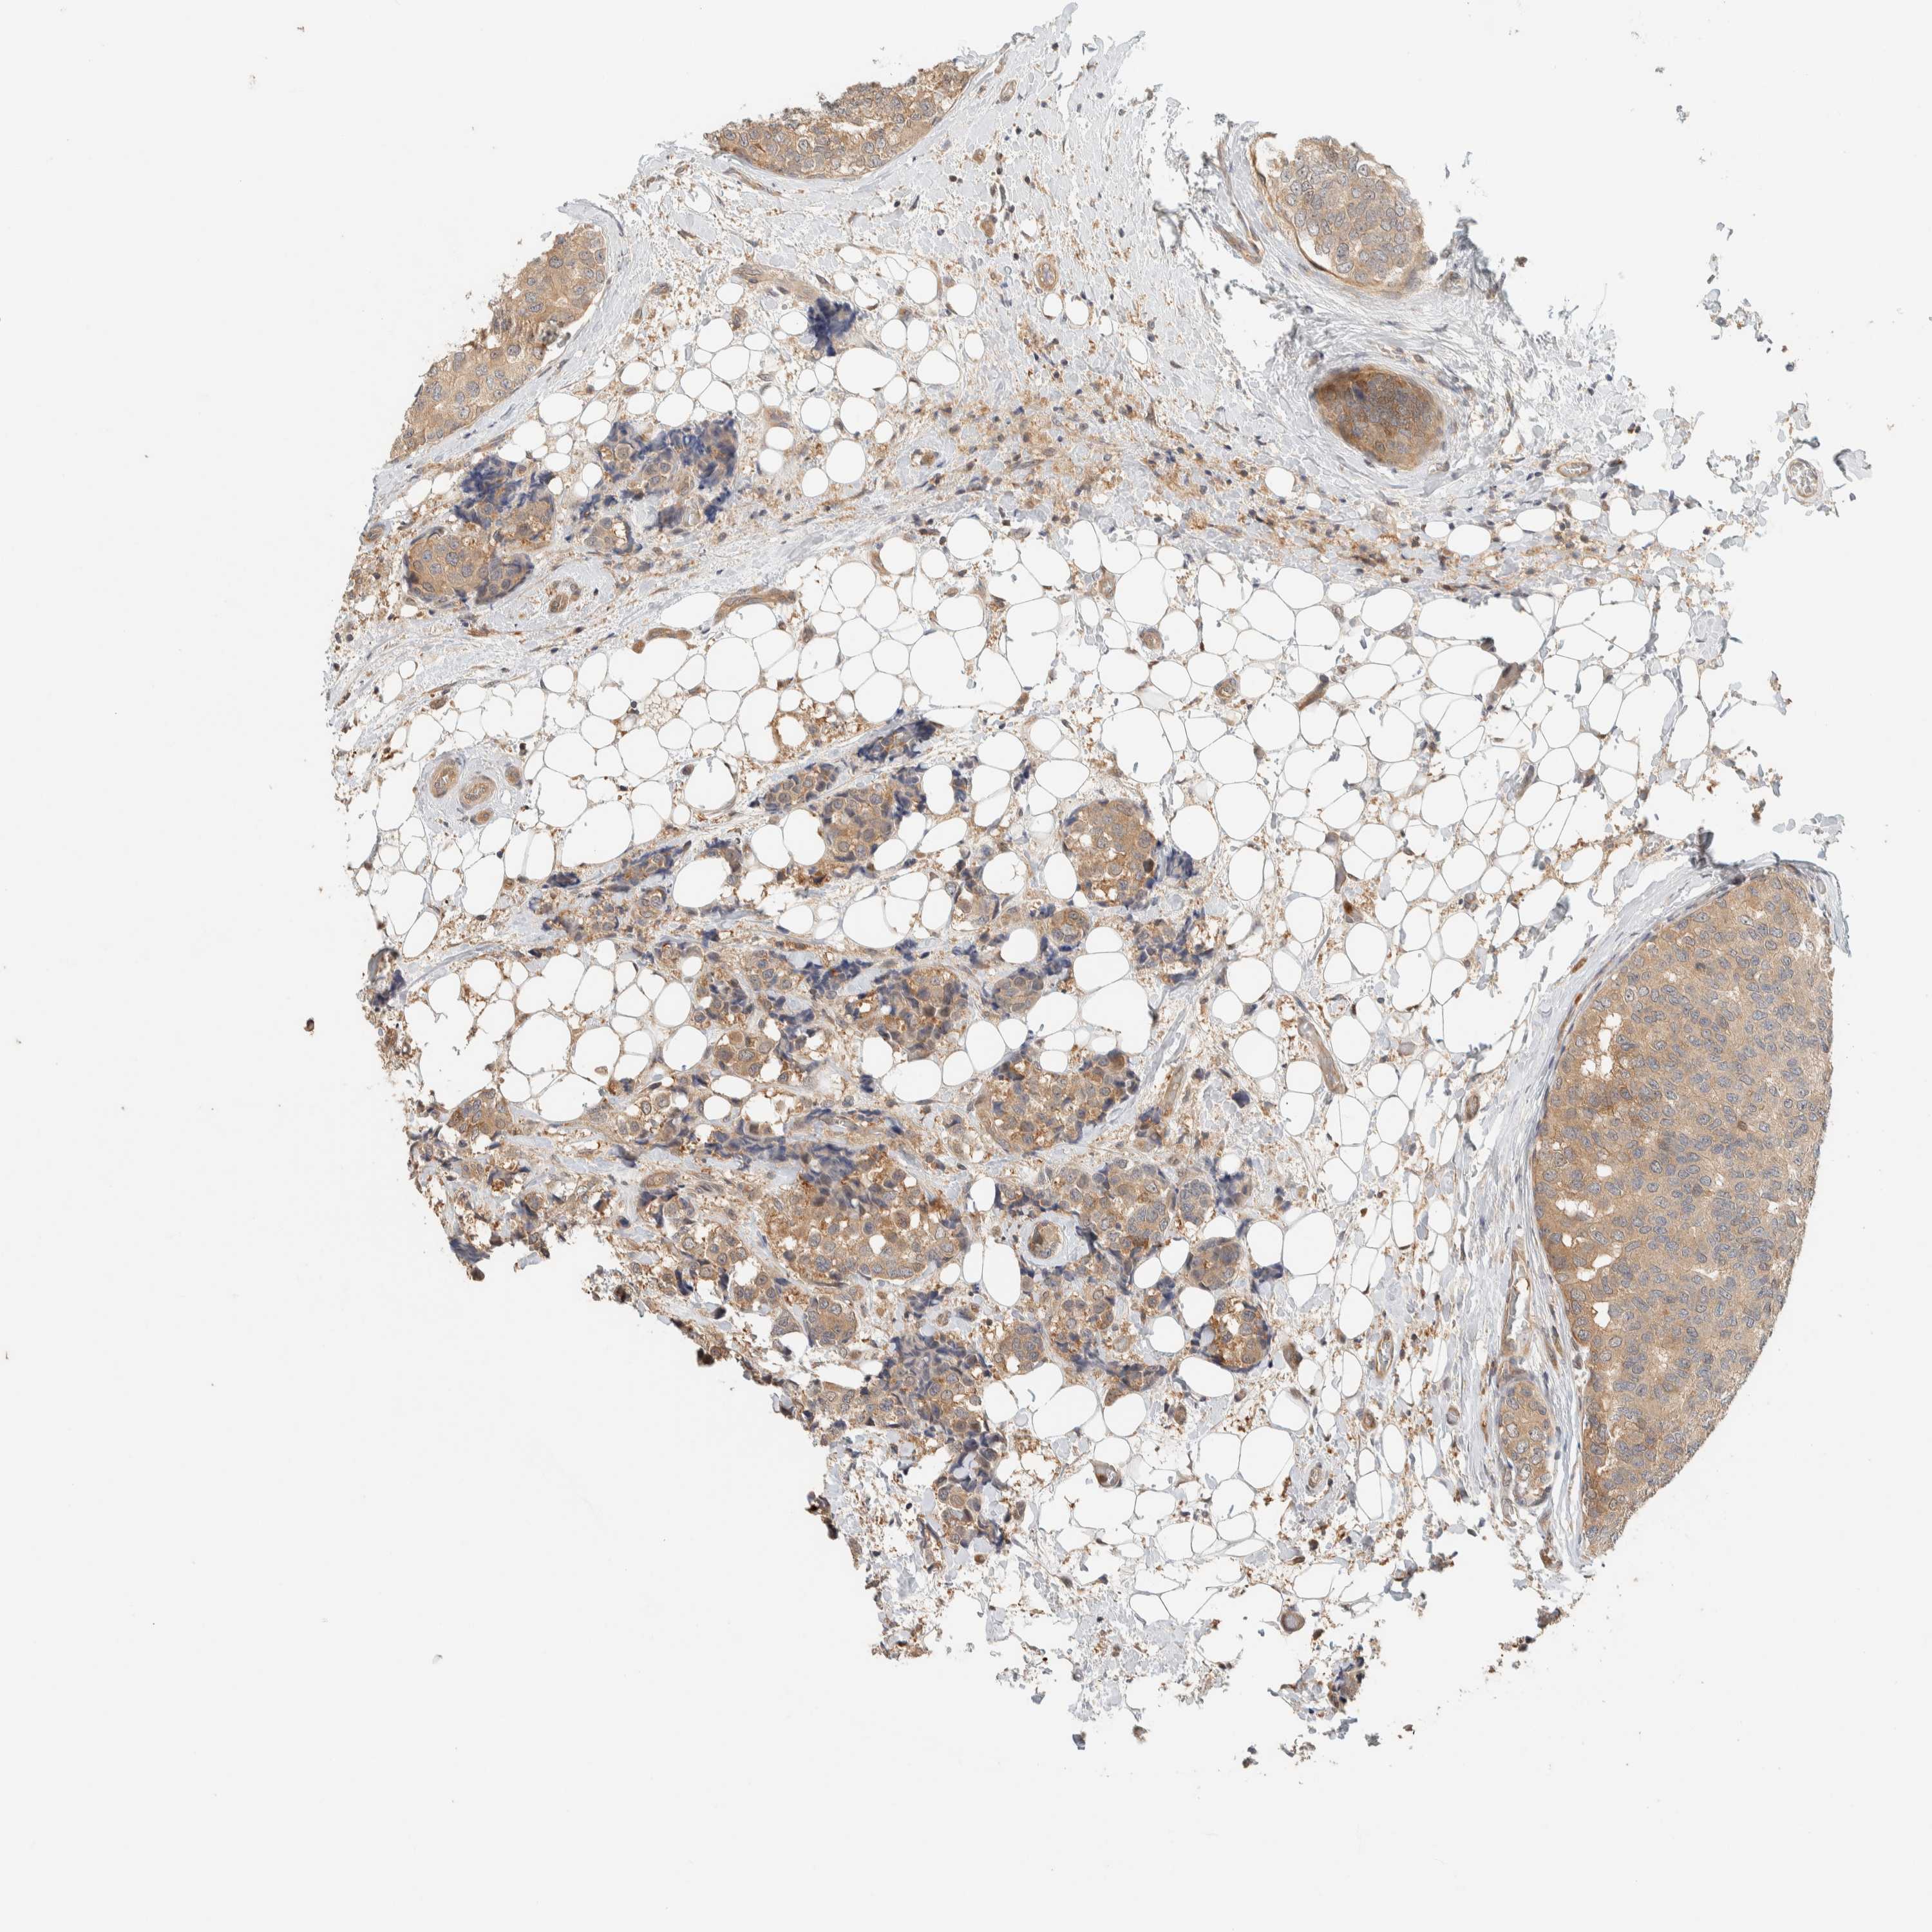

BRCA TCGA BRCA VALIDATION PROTEIN EXPRESSION